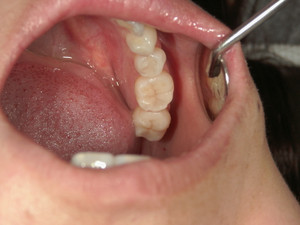

下の写真は、大臼歯奥の2本にハイブリッドインレーが入っています。(自由診療の審美)の

治療となります。こちらも五年半前の治療となります。長い間変色も少なくするには、治療の

一つ一つを丁寧に行うことは、当たり前の事ですが、患者さんの普段の歯ブラシや定期的な

メンテナンスも重要です。虫歯治療、歯周病治療は、まず、徹底的に治して定期的に口腔内の

清掃メンテナンスが歯を長持ちさせるコツですよ!!